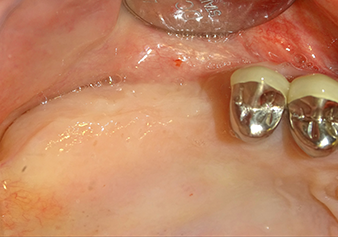

A 49-year-old female patient, a non-smoker and with nothing remarkable in her general medical history, was referred to our oral surgery practice for surgical extraction of tooth 16 and subsequent implantation. After the extraction, the patient experienced mild sinusitis trouble with the resultthat we initially waited six months before carrying out the measure. The residual bone height at the planned implant position measured 3-4 mm (Fig. 1 and 2).

To move the augmentation material in the direction of the maxillary sinus atraumatically, the implant was inserted very slowly by hand (Fig. 9). In the process, the membrane was pushed in the cranial direction once again. After two months, the surgical site healed without irritation. Six months later, the x-ray check showed a significant increase in opacity as an indication of ossification (Fig. 10). The prosthetic restoration was carried out with a metal-ceramic crown.